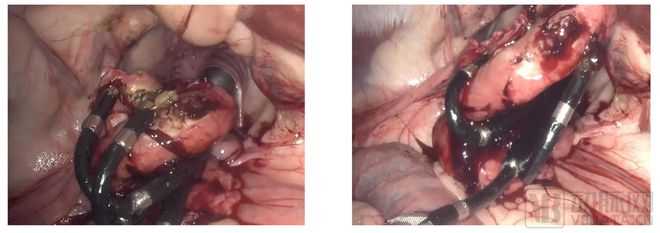

视通医疗团队与上海某知名三甲医院妇科专家们携手,成功完成妇科自然腔道机器人的首例活体动物实验,包括经阴后穹窿穿刺、输卵管结扎和卵巢切除等一系列手术步骤。雌性绵羊动物模型作为研究对象,涵盖了女性生殖器官的关键结构,包括阴道、子宫和卵巢等。

在穿刺入路的操作中,采用了视通医疗自研的穿刺套件,该套件具备扩张、穿刺、引导和伤口保护等功能,确保经后穹窿入路顺利进入骨盆腔。视通医疗设计精巧的柔性臂,显著降低了对肠管组织的穿刺和压缩风险,充分发挥了其在解剖入路方面的独特优势。

柔性臂在经阴入路后,展现了超过180°翻转能力,通过手术的视角和器械位置调整,可以在狭小的手术空间内模拟传统腔镜手术的视野效果,为手术提供了更广阔的操作空间。

在输卵管结扎手术中,视通医疗机器人展现了其卓越的电外科性能。通过精准的机械臂操作,成功定位绵羊的输卵管位置,暴露输卵管韧带。借助电凝切割技术,完成手术同时最大程度地减少了周围组织的热伤害,为盆腔内的器官提供了安全保护。

在卵巢切除手术中,自然腔道机器人的柔性臂设计发挥了关键作用,给医生提供了更多操作选择,实现了组织的有效提拉。机械臂协同操作使卵巢韧带暴露,血管和神经组织清晰可见。通过局部撑拉和间隙游离操作,有效暴露出卵巢动脉和静脉,运用电凝技术进行阻断,实现了无血手术。